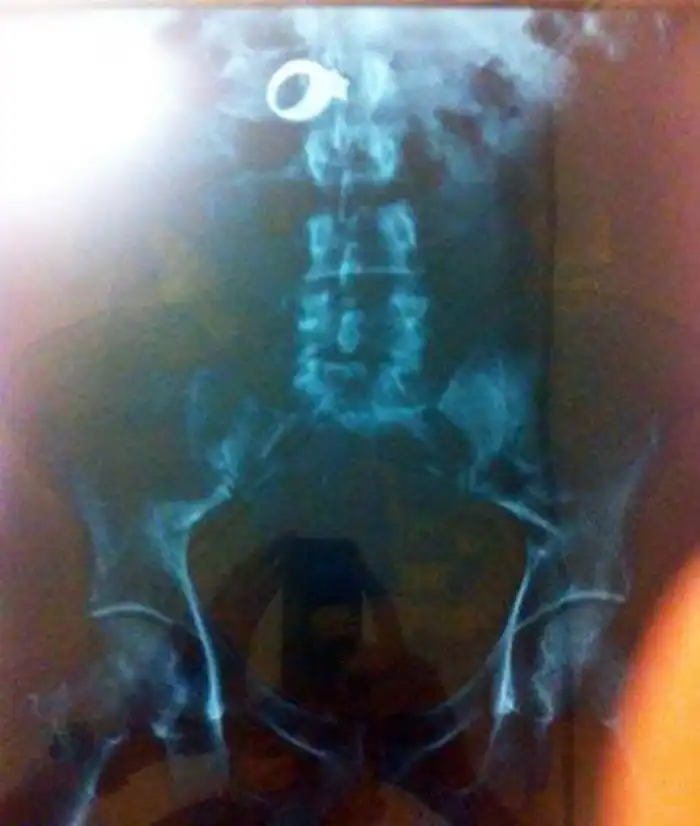

Рентгеновский снимок кольца с бриллиантом внутри 30-летнего Уилфредо Гонзалез-Круз (Wilfredo Gonzalez-Cruz), из Чикаго. Мужчина украл кольцо из дома женщины в Сисеро (Cicero) и затем проглотил его.